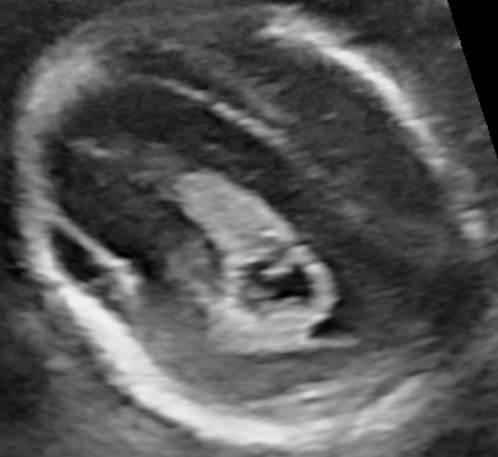

Diagnosing Polyhydramnios

The gestational week does not influence the diagnosis of polyhydramnios. The size of the uterus could be suggesting of this condition, however the diagnosis should be made during ultrasound examination. There are two common ways to estimate the volume of the amniotic fluid:

- Single Deepest Pocket (SDP). A vertical measurement in the deepest amniotic fluid pocket. Values below 2 cm indicate oligohydramnios, values over 8 cm indicate polyhydramnios (8-11: mild, 12-15: moderate, > 16: severe). In multiple gestation, a range of 3–8 cm is defined as normal. Another technique is the

- Amniotic Fluid Index (AFI). This is the sum of vertical measurements of all four quadrants (polyhydramnios usually >24).